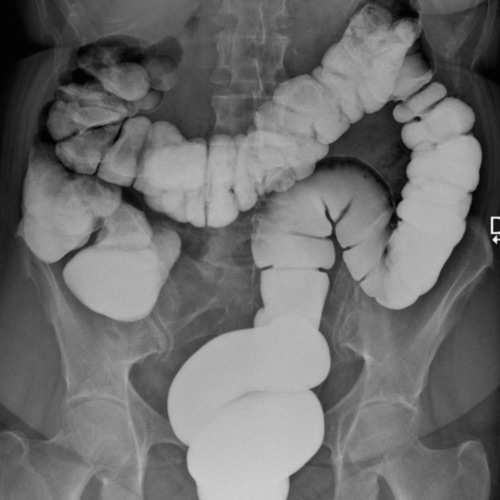

Normalement la colon est un tube cylindrique a

paroi lisse comporte en cinq partie . Le colon droit depuis

le caecum debute le ceocum jusqu'a l'angle droit , le colon

transverse , le colon gauche , le sigmoide et le rectum

Le colon est

en aspect segmentation haustrale a bien

visible de droite a gauche . Epaisseur des

haustrations ne depassent pas de 2 a

3mm . Calibre du colon etre inferieure de 5

a 6cm

Image une

lavement baryte mono de contrast . La region ileo -

ceacal est si nette . Une partie de ileon peut

voyait . Appendice se presente dans cette cas |

Lavement baryte ( mono

contrast ) : Image radiologique normale du colon :

Caecum , colon ascendant , angle droit , colon

trasverse , colon gauche , colon sigmoide et rectum

. |